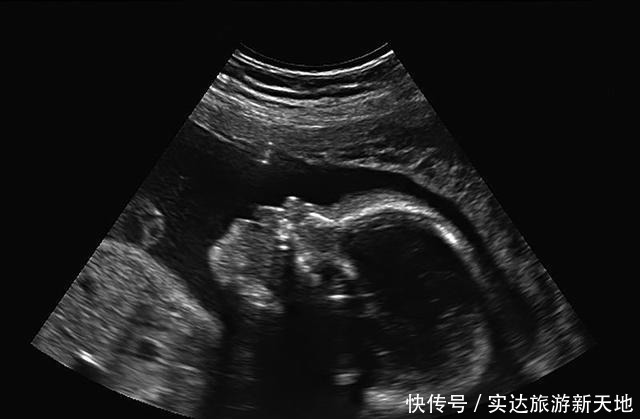

1、宝宝的胎心率宝宝的胎心正常的范围是每分钟跳动120到160次,如果宝宝心跳过快或过慢都是不正常的,需要进一步检查。但宝宝心跳慢过慢也可能是因为宝宝正在睡觉,可以过几天再去检查确定一下。2、子宫羊水量(AMN)羊水量直接影响宝宝的安危,医生通常是通过测量羊水深度来确定羊水的多少。羊水深度正常范围是3-8cm。羊水量比正常范围稍高或者稍低都是不正常的,妈妈们要重视起来。羊水量少的情况,医生会建议妈妈进行水分,每天大概要喝2000ml左右的白开水。如果是非缺水情况造成的羊水少,需要医生的外界帮助,恢复正常。

3、胎儿头部和股骨长医生在测量宝宝的头部时,一般都会测量很多组数据。为了避免产生一些误差,一般都会取数据的中间值。宝宝足月头部小于或等于10cm,顺产会更好。除了头围,还要测量胎儿的腿长,医生会根据头围和腿长,来大概预测宝宝现在的重量。宝宝体重不达标,就要加强营养。但因为测量是人工测量,所以会有一定小误差,影响不大。

4、胎盘成熟度怀孕9个月的时候开始,准妈妈们再检查,检查单上出现胎盘分级的新数据。胎盘的级别可以分为0-3级。在怀孕初期胎盘都是0级的;胎盘基本成熟显示1级;胎盘已经成熟显示2级;胎盘如果显示3级代表已经进入老年期,也就说到了瓜熟蒂落的时间。一般怀孕九个月以后,胎盘已经成熟,作用已经渐渐减弱,尽快生下宝宝也对孩子比较好,否则宝宝胎盘产生的废弃物就会影响宝宝的健康。